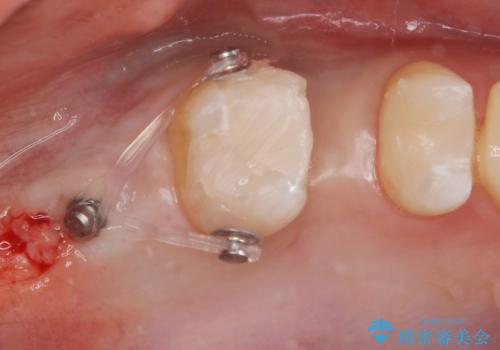

なので親知らずを抜歯して、一番奥の歯を部分矯正(upライト)をして倒れ込んでいる歯を起こしてスペースを作り、ブリッジの治療を行いました。

- ジルコニアクラウンブリッジ(スタンダード)・仮歯・部分矯正(upライト) 50.6万円費用は治療当時の料金となります